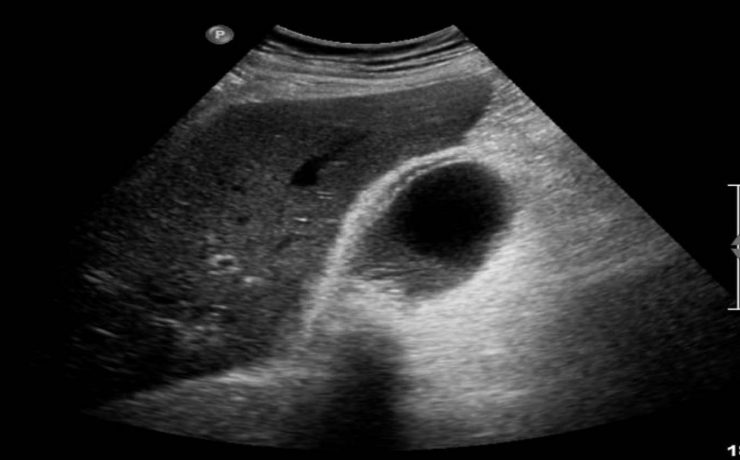

Correlación ultrasonográfica e histopatológica de los tumores de ovario

El cáncer de ovario, constituye el 2 % de las afecciones malignas de la mujer con una alta mortalidad, aproximadamente las dos terceras partes se presentan con lesiones muy avanzadas en el momento del examen imagenológico,1-4 trae por consecuencia una supervivencia menor de la paciente y un aumento del costo